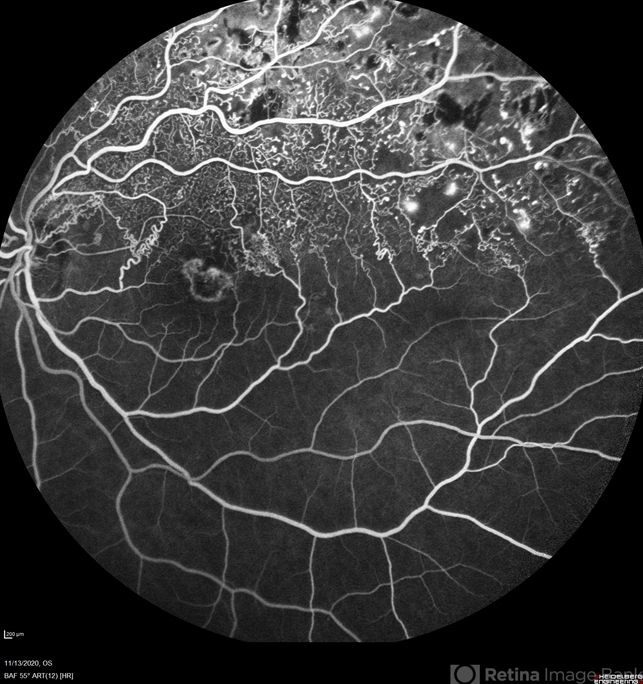

- branch retinal vein occlusion (BRVO)

Heidelberg Spectralis - Description

- 77-year-old woman with a superior branch retinal vein occlusion.